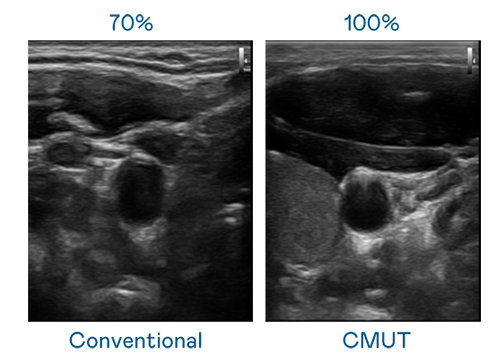

CMUT 技术是一种用电容式微机电元件来产生超音波讯号的技术。与传统 PZT 压电式技术相比,CMUT 频宽增加 30%,更宽频的超音波讯号让影像解析度大幅提升,是实现高影像品质医疗超音波扫描、促进精准医疗发展的关键技术。

超音波影像的解析度高低,首先取决于探头能发出的讯号频宽。JJB电竞 CMUT 可提供高清晰的超音波讯号,提供高频宽、高灵敏度、影像纹理细节更高的超音波影像,协助医护人员缩短影像判读时间及利用精准的医疗影像进行诊断。